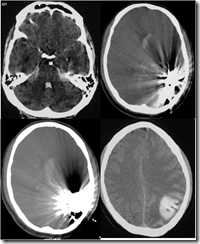

However he suddenly developed seizures and right sided weakness 4 hours later. An urgent CT showed hematoma and IVH.

A 14-yrs old boy presented with sudden severe headache and loss of consciousness

CT head showed subarachnoid hemorrhage

DSA was done which showed extensive vasculopathy and multiple aneurysm formations

The aneurysm on left Distal ACA was coiled, however there was extreme narrowing of the parent artery during the procedure and the patient developed left ACA territory infarcts post procedure